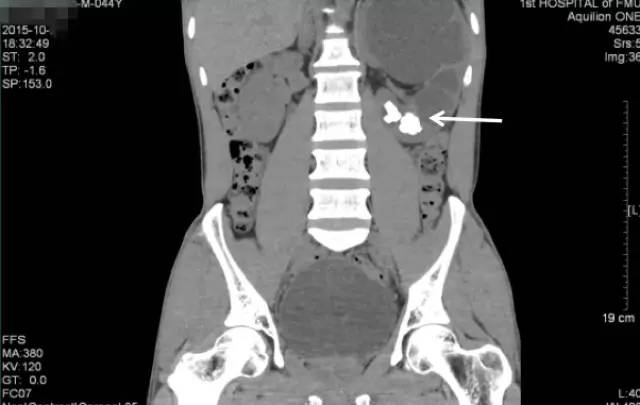

柯先生慕名来到我的门诊就诊。简单询问病情后,我给他开了KUB的检查单,KUB结果如下:

可见相当于左肾区(红框内)多发结节状密度增高影聚集,部分呈鹿角型。这是一个非常复杂的肾结石,虽然还没有做CT检查,但已可以判断这个肾脏功能一定受损严重,当时就建议柯先生住院微创手术治疗。

第一次来福建医科大学附属第一医院KUB检查结果

可见相当于左肾区(红框内)多发结节状密度增高影聚集,部分呈鹿角型